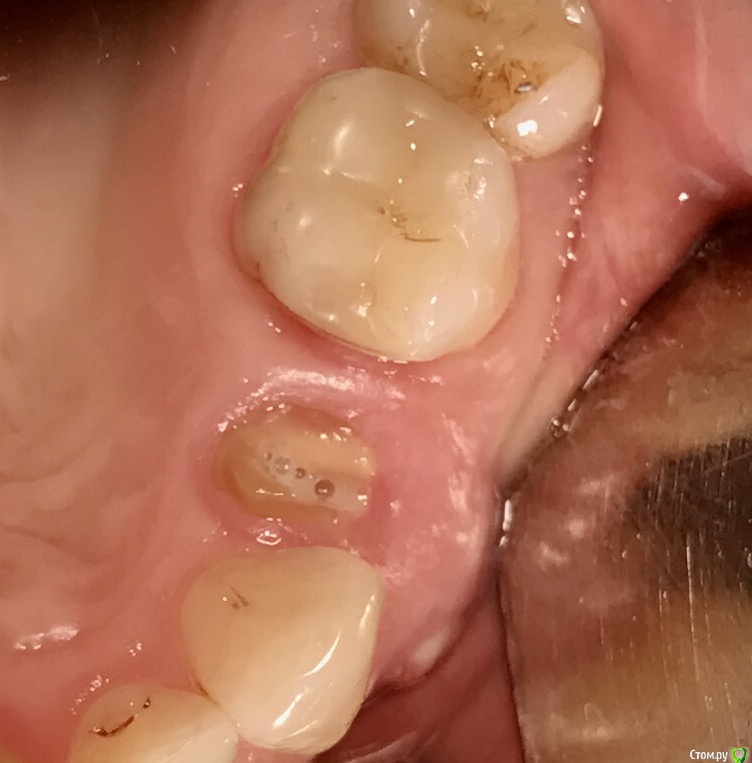

колесников Опубликовано 25 февраля, 2017 Поделиться Опубликовано 25 февраля, 2017 Здравствуйте коллеги! Представляю вашему вниманию этот клинический случай.В ноябре 2016 обратилась пациентка с жалобами на выпадение ортопедической конструкции в обл 24. Объективно: корни 24 не состоятельны. ,на десневом крае в проекции 24 свищевой ход с гнойным отделяемым.На КТ резорбция вестибулярной компактной пластинки и деструкция костной ткани в области щёчного корня.Приняв во внимание крайне негативное отношение пациентки к каким бы то ни было хирургическим вмешательствам и высоким эстетическим требованиям,было решено пойти на немедленную имплантацию .Снимки в день вмешательства,через 7,14 дней и 3мес.Имплант Astra tech profile 4.5х11мм. Сст с бугра вестибулярно. Вместо графта губки Коллапола (не вспомню причину,либо не было в наличии,либо отказ пациента). 15 Ссылка на комментарий